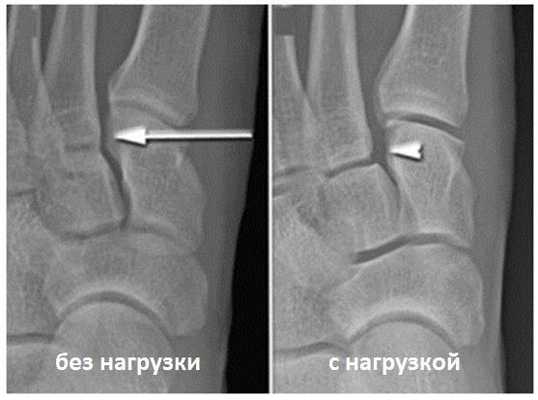

Для инструментальной диагностики используются рентгенограммы с\без нагрузки в сравнении со здоровой стороной, при их малой информативности рекомендовано выполнение стресс-рентгенограмм, аналогично приведёному выше тесту на нестабильность.

При рентгенографии все снимки выполняются в сравнении со здоровой стопой. Существует несколько основных рентгенологических признаков повреждения сустава Лисфранка. 1. Отсутствие параллельности медиального края основания 2-й плюсневой и медиального края медиальной клиновидной кости 2. Расширение между основаниями 1 и 2 плюсневых костей 3. Наличие костного фрагмента в области основания 2-1 плюсневой кости 4. Тыльный подвывих на боковой проекции 5. Разрыв линии предплюсне-плюсневого сочленения.

![вывих в суставе лисфранка классификация]()

• Чувствительность рентгенографии повышается при исследовании стопы с нагрузкой (в положении пациента стоя или при наружной ротации стопы)

• Латеральное или дорсальное смещение основания 2-й плюсневой кости относительно промежуточной клиновидной кости

• Увеличение расстояния между 1-й и 2-й плюсневыми костями:

о Признак сильно зависит от того, в каком положении находится стопа (пронация или супинация), и потому не является достоверным

• Отрывной перелом медиального края основания 2-й плюсневой кости:

о В данной области находится точка прикрепления связки Лисфранка

• Уплощение продольного свода стопы:

о Выявляется лишь на уровне предплюсне-плюсневого сустава

• Изменение расстояния между клиновидными костями не является чувствительным признаком повреждения связки Лисфранка:

о Сильно зависит от того, в каком положении находится стопа (пронация или супинация)4. КТ при повреждении связки Лисфранка: